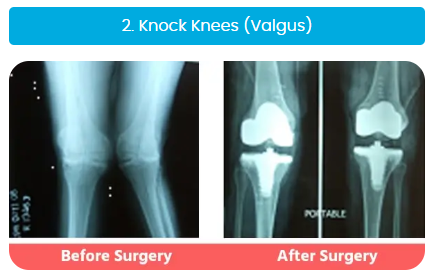

Complex Knee & Hip Replacement Surgeries

Our surgeons are highly experienced in handling complex cases like bow legs (varus), knock knees (valgus), or wind-swept legs, and have considerable expertise in revision joint replacement surgeries.